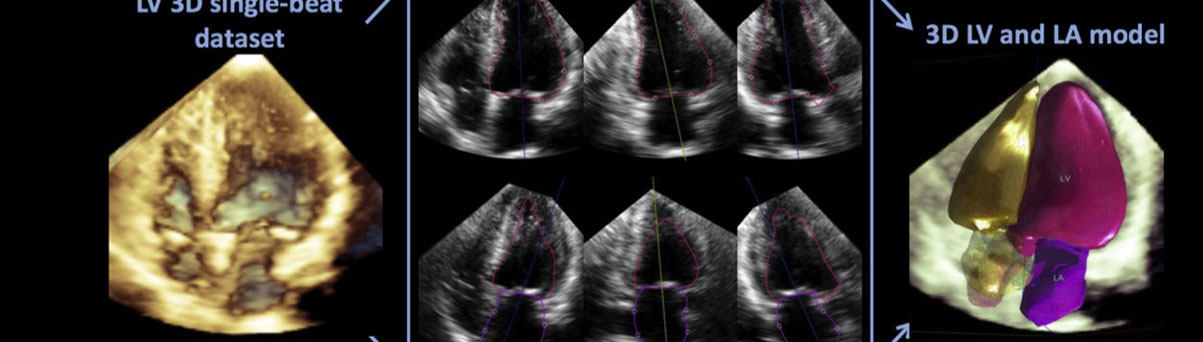

• Ecocardiograma Doppler 3D para paciente adulto y pediátrico. Es un examen que emplea ondas sonoras para crear una imagen en movimiento del corazón.